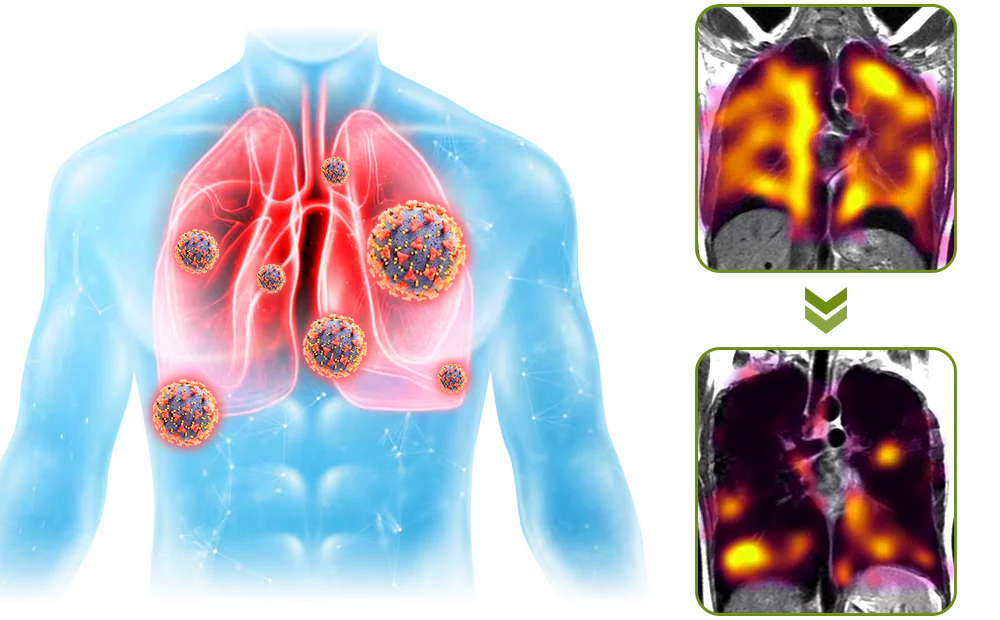

The HZA™️ BreathDetox Herbal Lung Cleansing Spray offers a convenient and effective solution for clearing mucus and waste from the lungs, as well as purifying and cleansing the upper respiratory passages. It is specifically designed to repair damage caused by allergies, asthma, dust, and smoking within a span of 8 weeks. This innovative product provides individuals with weakened respiratory systems an effortless opportunity to restore their breathing capacity.

Clinical trials and surveys have yielded compelling evidence supporting the effectiveness of this medication in the treatment of chronic pharyngitis, pulmonary nodules, and pulmonary dysfunction. Furthermore, it has demonstrated notable efficacy in managing environmental allergies and asthma. Additionally, thorough verification has established the significant role of the spray in both treating and preventing the consequences of pulmonary inflammation. These findings contribute to the growing body of evidence highlighting the medication’s effectiveness across a range of respiratory conditions.

The mechanism of the HZA™️ BreathDetox Herbal Lung Cleansing Spray involves delivering a fine mist directly into the passages and airways, ensuring optimal effectiveness and targeted action. When you apply the spray into your mouth, it releases a gentle and precise mist that coats your respiratory system. This targeted approach enhances the product’s overall performance in promoting lung health and cleansing the respiratory system.